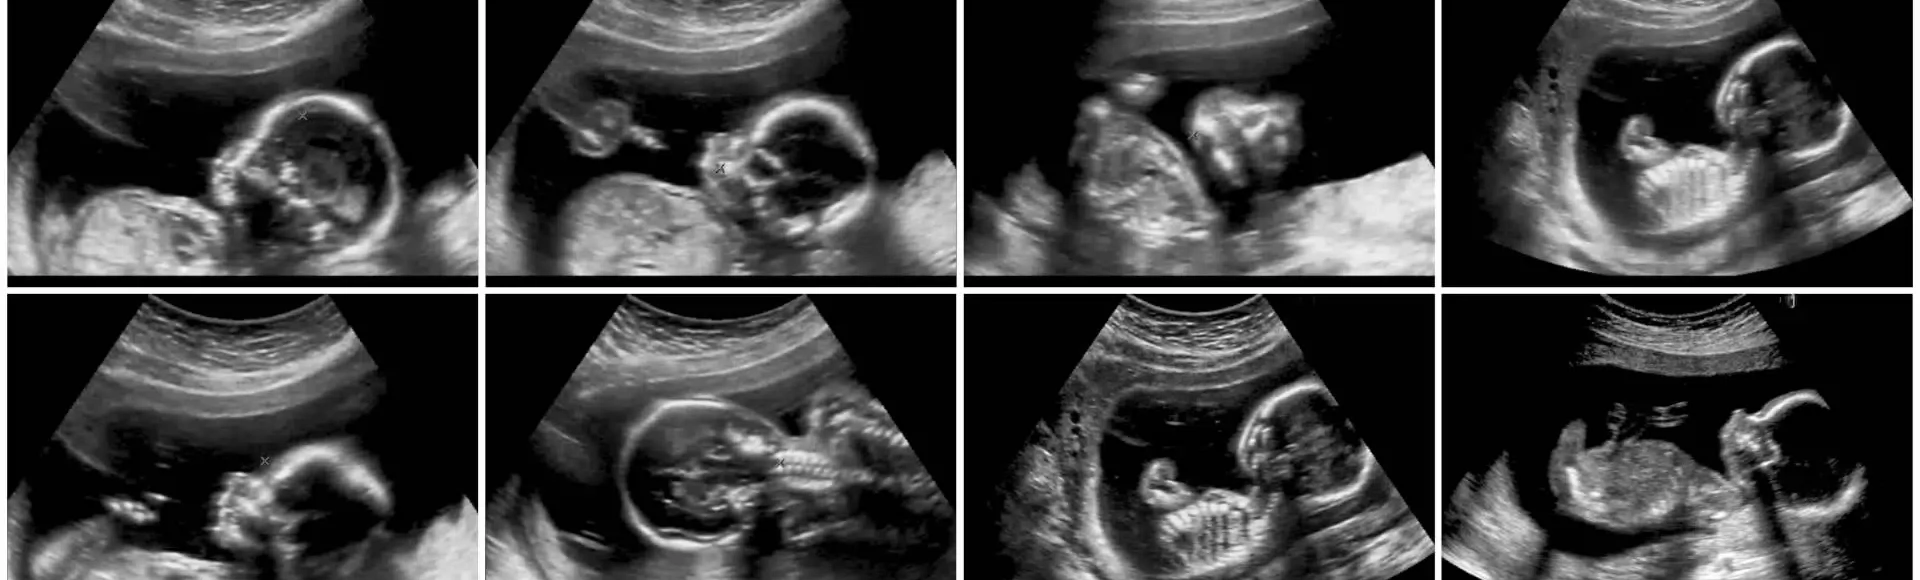

In de 'Bijscholing Echoscopie Basis 1e trimester' gaan we in een snel tempo door de lesstof. Aan bod komen de theorie en de praktijk van het vaginale- en abdominale echo-onderzoek. Tijdens deze dagen staat de vitaliteit en de datering van de zwangerschap centraal.

Je verbetert je vaardigheden aan een echoapparaat. Dit doe je grotendeels 'hands-on' in kleine groepjes. Je oefent tijdens de lessen op live-modellen. Bij het aanleren van de transvaginale echografie maken we gebruik van de scantrainer. Dat is een simulator van transvaginale echografie.